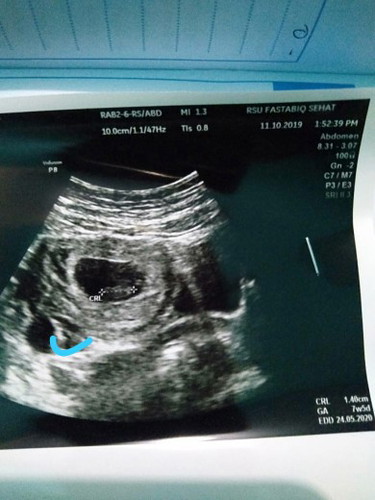

Assalamualaikum.. Bun, sharing dong.. saya hamil 7w5d trnyata dikehamilan saya ada kistanya, yg dicentrang wrna biru.. kata dkter gpp, bunda ada gk yg ngalamin kyak saya.. trus kistanya bisa hilang apa gak ? Saya khawatir, jdi tkut knpa2..

Klo dokter bilang gpp berarti itu kista kecil bun, gk ada masalah . Sy juga alami itu, semangat bun, jgn byk pikiran.